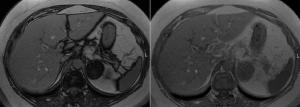

Adrenal Lesion Discovered in 50-Year-Old PatientPublished: August 12th 2013 | Updated: